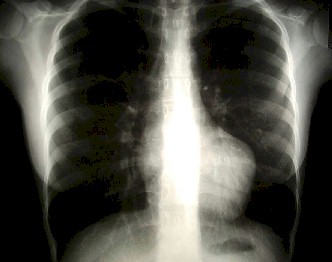

1. Radiografía Tórax: se evidencia cardiomegalia, rectificación del borde izquierdo del corazón y campos pulmonares normales.